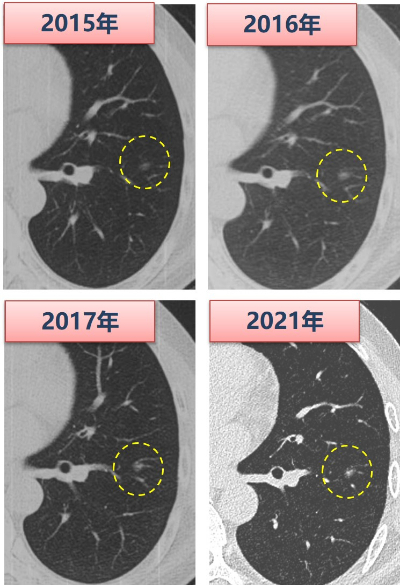

图4 长期随访的磨玻璃结节实性成分增加后手术干预

我们知道,磨玻璃结节绝大部分都是惰性增殖的表现,生长非常缓慢,往往需要四五年的时间,才会发生明显变化。以一个长期随访的实际病例来说明。这个患者2015年在外院体检发现了一个小的纯GGO,此后逐年在外院随访,2017年GGO并没有明显的变化。此后患者因为工作调动,加上疫情原因耽搁了随访,再次复查时我们对比最早CT判断,结节直径虽然没有明显增长,但中心密度增高,出现了一点实性成分,进行了胸腔镜手术干预(图4)。术后病理提示是微浸润腺癌,预后很好。这个病例说明,部分小GGO在随访中可能出现进展,表现为直径增长或实性成分增加,这个过程可能很漫长,我们可以尽可能的推迟接受胸部手术的创伤,规范的随访观察是很安全的。